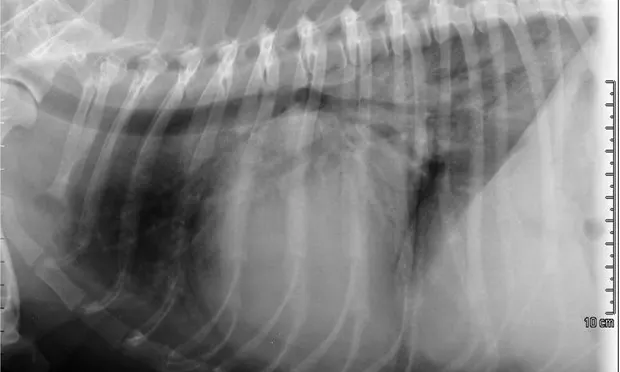

FIGURE 2A

Right lateral thoracic radiograph

A sinus rhythm (HR is ~150 bpm) and left ventricular enlargement pattern were noted on ECG: the sensitivity was decreased to 5 mm/mV, and R waves measured ~3 mV (upper end of normal R-wave height is 2.5 mV). Thoracic radiographs revealed severe left atrial enlargement with moderate left ventricular enlargement. There was a moderate interstitial to alveolar pulmonary pattern most pronounced in the caudodorsal lung fields, which is consistent with left-sided congestive heart failure resulting from degenerative mitral valve disease.